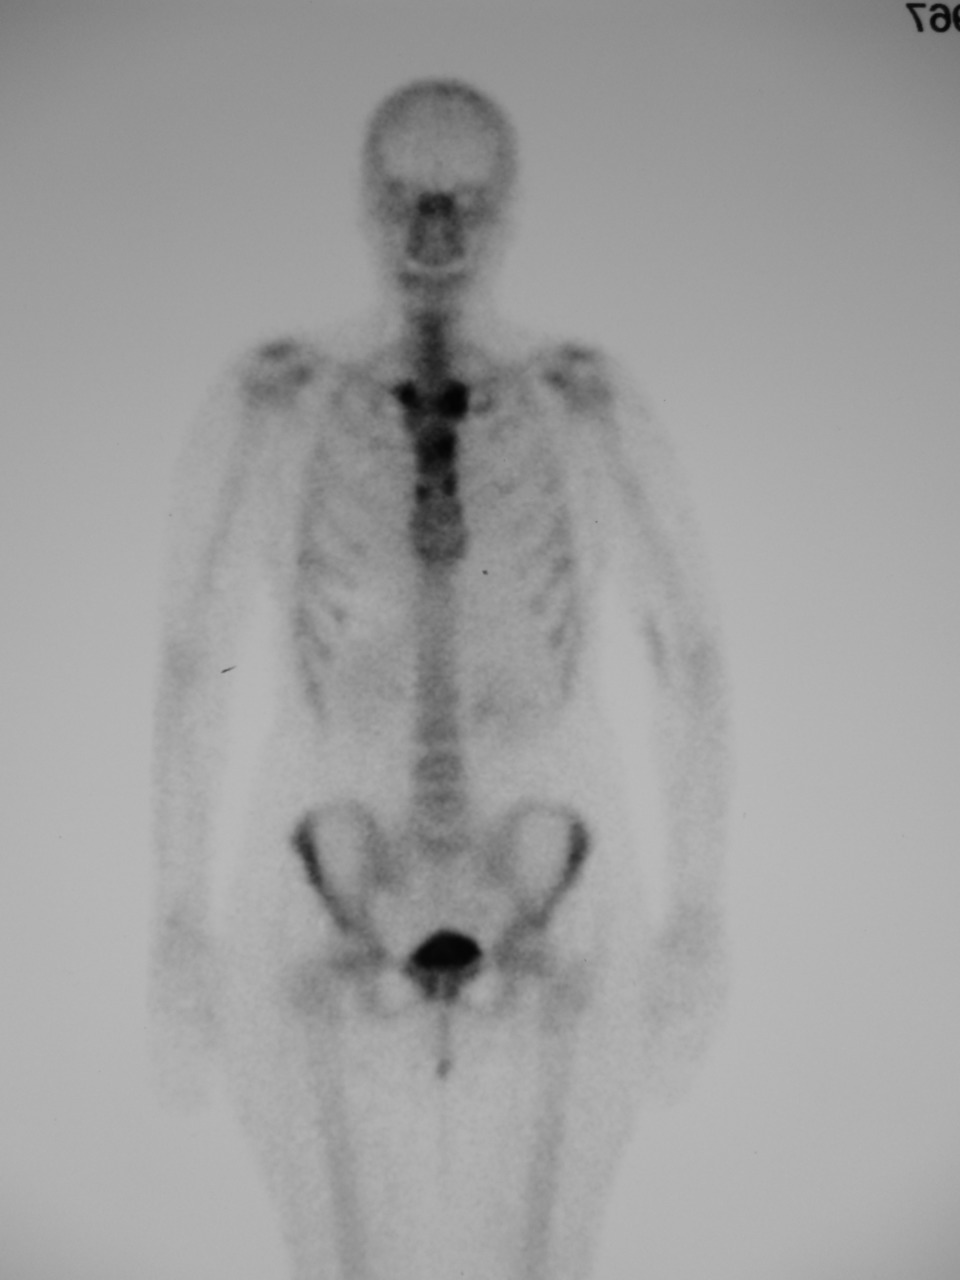

Il s’agit d’un syndrome de SAPHO.

La pierre angulaire du diagnostic correspond à une atteinte osseuse inflammatoire chronique très particulière, volontiers multifocale, donnant lieu à une réaction hyperostosante pseudo- pagétique. Les localisations les plus fréquentes se situent à la paroi thoracique antérieure (articulations sterno-claviculaires et manubrio-sternale), au bassin (articulations sacro-iliaques, symphyse pubienne) et au rachis.

La scintigraphie osseuse, comme présentée ici, permet une cartographie lésionnelle précise des foyers d’ostéite.